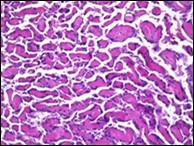

On microscopy, superficial squamous epithelial surface is intact. Sub-epithelial connective tissue stroma exhibits slit-like, vascular spaces. Upon extended magnification, multiple, intravascular papillary projections encompassed within a hyalinised stroma are discerned. Centroidal calcification appears in combination with intravascular, papillary endothelial cell proliferation, lined with singular layer of endothelial cells devoid of cytological atypia6, 7.

Characteristically, the vascular neoplasm denominates numerous papillae within blood vessels. Papillae are coated with singular or dual layer of flattened endothelial cells with an encompassing hyalinised, fibrous tissue core. Vascular lumen is distended with thrombosis. Foci of haemorrhage with fibrinous and purulent exudate are discerned. Tumour perimeter depicts inflammatory granulation tissue. Cholesterol clefts and focal reactive bone formation may concur. Extraneous squamous epithelium may be discontinuous and ulcerated. The neoplasm is devoid of features of malignancy4, 6.

Numerous micro-calcifications can be observed within the lesion which may engender vascular occlusion and tissue necrosis6. Figure 1, Figure 2, Figure 3, Figure 4, Figure 5, Figure 6, Figure 7, Figure 8.

Figure 3.Papillary endothelial hyperplasia exemplifying papillary configuration with endothelial cell layering and a superimposed stratified squamous epithelial lining 12.